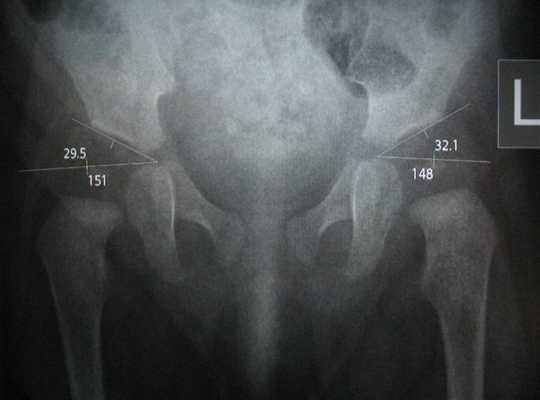

Какие инструментальные методы исследования привлекаются в диагностике подвывиха тазобедренного сустава? Прикладной является рентгенография сустава в двух проекциях. На рентгенологических снимках выявляют смещение головки плечевой кости из вертлужной впадины. Этого метода достаточно, чтобы выявить нарушение и определиться с нюансами врачебной тактики.

Амплитуда движений в тазобедренном суставе (активные и пассивные) измеряется с помощью гониометра и документируется. Эти измерения являются базовыми и помогают определить, насколько эффективна программа лечения.

Методом выбора является рентгенография тазобедренного сустава в прямой и боковой проекциях. Это позволяет исключить переломы. Однако, в некоторых случаях, даже если рентгенологическая картина в норме, требуется проведение дополнительных исследований, например, КТ или МРТ тазобедренного сустава, с целью исключения скрытых переломов или повреждения мягких тканей.

В сложных случаях КТ может быть полезна для получения дополнительной информации, которая необходима при планировании операции. Также стоит учитывать, что интерпретация рентгеновского снимка будет осложнена у пожилых людей наличием других состояний, например, дегенеративных процессов.